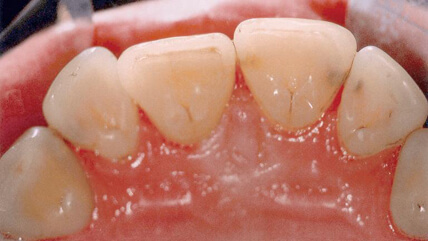

コーヒーや紅茶、タバコのヤニなどの着色汚れが落ち、本来の白い歯と輝きが戻って表面がツルツルになります。1回でかなりきれいになります。

- エアフローでの治療後

- 歯と歯の間のむし歯がわかるようになりました。このように、口腔内の問題が見過ごされるのを防ぐことが出来ます。